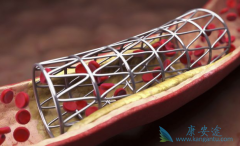

心脏支架作为现代心血管医学发展中的一个里程碑,确实在冠心病的治疗中发挥着非常重要的价值。 生物可降解支架 给冠心病介入治疗带来了新的革命。但是生物可降解支架真的能成为心血管患者的福音吗?目前心脏支架主要分为不可降解支架和完全降解支架两个 ...

生物可降解支架 安全吗?其实早在20世纪90年代初,就已经提出生物可降解支架的概念,但发展没有金属裸支架和药物洗脱支架快,最终被药物洗脱支架所替代。目前药物洗脱支架长期随访发现潜在的支架内血栓风险,最近10余年生物可降解支架科技和材料学取得 ...

为了改善冠心病介入治疗短期和长期的疗效与安全性,所以研发了支架。第一代支架是金属裸支架,使冠心病介入治疗前进了一大步,使介入治疗变得非常安全,当血管发生严重狭窄时单纯球囊扩张预处理后,再用支架把血管完全撑开,就能解除心肌缺血危险,而且 ...